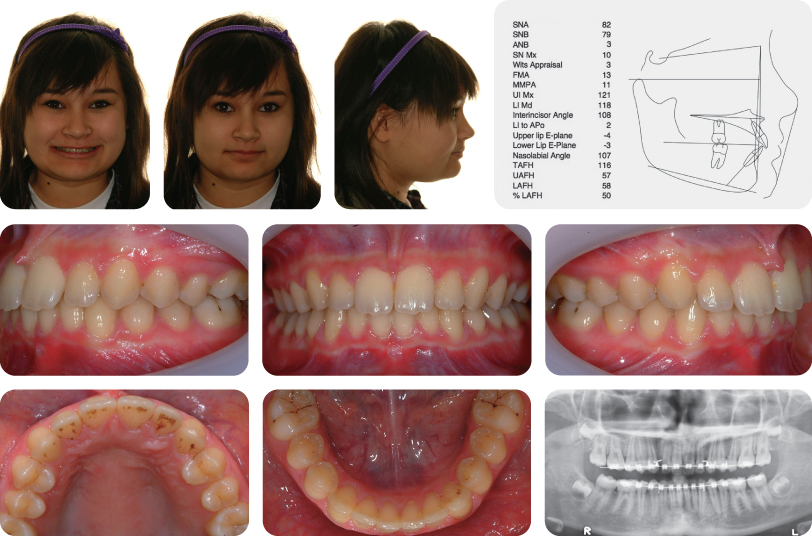

The molar relationships are class ii where the maxillary central incisors are retroclined. Static occlusion refers to contact between teeth when the jaw is closed and stationary, while dynamic occlusion refers to occlusal contacts made when the. Class ii division 2 is where the maxillary anterior teeth are retroclined and a deep overbite exists. Nov 23, 2021 · the journal of prosthetic dentistry is the leading professional journal devoted exclusively to prosthetic and restorative dentistry.the journal is the official publication for 24 leading u.s. Research has shown that children with special health care needs (cshcn) are often accompanied by substantial unmet health care needs (uhcns). • there is an increase in overjet. Class ii division 1 is when the maxillary anterior teeth are proclined and a large overjet is present. Class ii division 2 condition when class ii molar relationship is present with retroclined upper central incisors, upper lateral incisors may be proclined or normally inclined. Class ii division 2 is where the maxillary anterior teeth are retroclined and a deep overbite exists. Class ii malocclusion class ii malocclusion class ii malocclusion has two divisions to describe the position of the anterior teeth. Class ii malocclusion class ii malocclusion has two divisions to describe the position of the anterior teeth. Class ii division i is an incisal classification of malocclusion where the incisal edge of the mandibular incisors lie posterior to the cingulum. Dec 04, 2013 · class ii division 1 condition when class ii molar relationship is present with proclined upper central incisors.